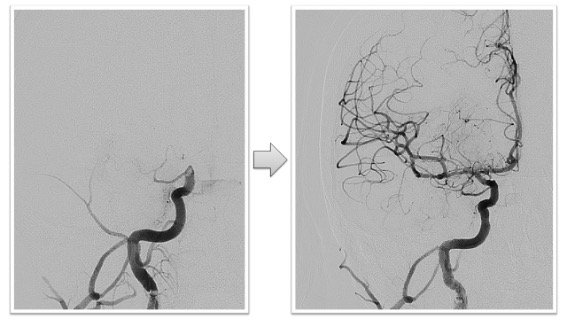

内頸動脈閉塞実例(*患者様の許可を得て掲載しています)

心原性脳塞栓症による左内頸動脈閉塞

右内頚動脈終末部の閉塞症例ですが、術後右内頚動脈から中大脳動脈、前大脳動脈などすべての末梢動脈への血流が回復しています。